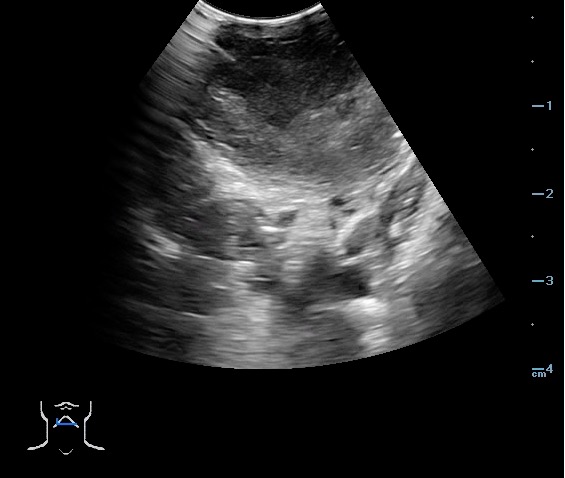

- Peritonsillar abscess is visualized as a hypoechoic or complex cystic structure

- Ultrasound-guided needle aspiration of a PTA:

- The depth of the abscess cavity from the mucosal surface should be noted to determine the length of the needle required to drain the abscess.

- Figure 45. and 46. PTA aspiration

- The carotid artery is seen as an anechoic tubular structure along the posterolateral aspect of the tonsil on ultrasound. Its relationship to the abscess cavity should be determined. Color Doppler can help locate the carotid artery.